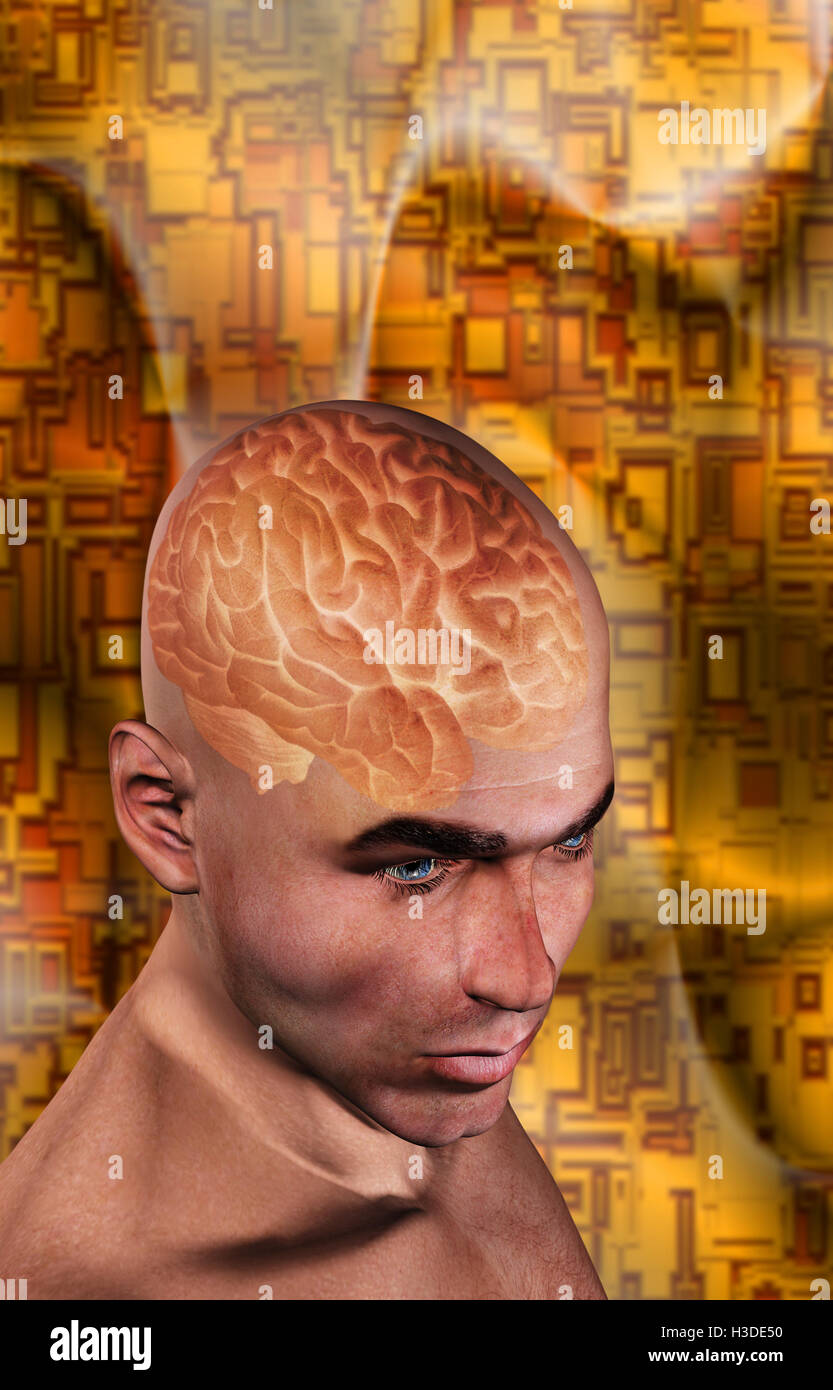

Männchen anatomie Stockfotos & Bilder

Suchergebnisse für Männchen anatomie Stock-Fotos & Bilder (86,080)